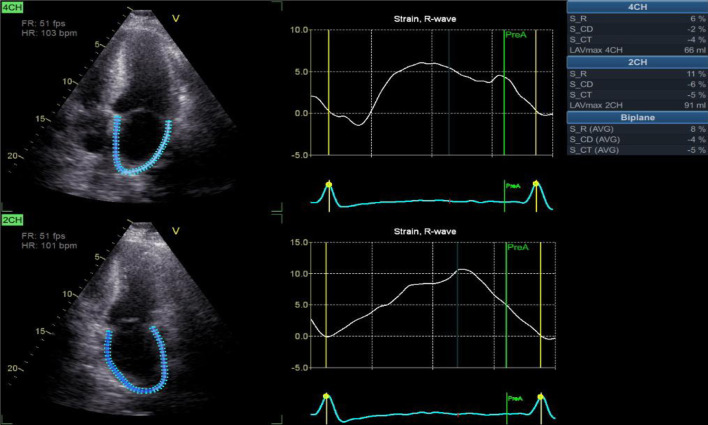

Results: By 2D echocardiography, patient group revealed significantly lower all LA functions vs. control group including reservoir (26 ± 4 vs. 43 ± 3, P < 0.001), conduit (-14 ± 2 vs. -25 ± 2, P < 0.001), and booster pump functions (-12 ± 2 vs. -18 ± 1, P < 0.001). PAP was significantly higher in patient group (42 ± 7 vs. 27 ± 4 in control group). LVGLS was significantly lower in patient group (-15±1.4% vs. -23±2% in control group). Using 3D speckle tracking echocardiography (STE), there were a significantly higher indexed maximum LA volume (Vmax indexed) (43.5 ± 5.6 vs. 28.7 ± 3.7, P < 0.001), but significantly lower left atrial strain at reservoir function (LASr) (24 ± 4 vs. 41 ± 3, P < 0.001), left atrial strain at conduit function (LAScd) (-13 ± 2 vs. -24 ± 2, P < 0.001), and left atrial strain at contractile function (LASct) (-11 ± 2 vs. -18 ± 1, P < 0.001).

Abstract Image